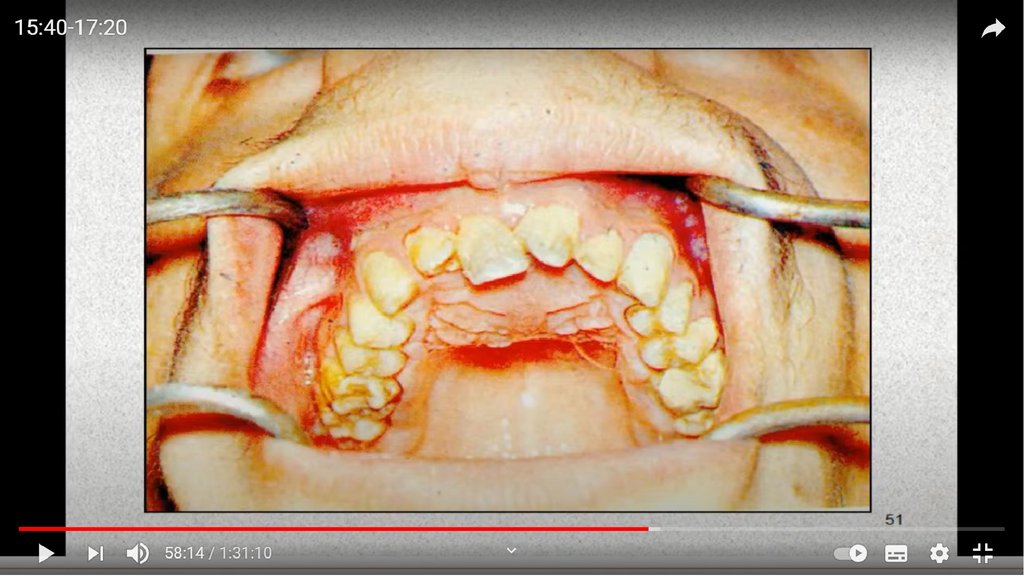

Рентгенографиясы:

Фиброзды форма: альвеолярлы процестің шетін

резорбциялау;

· Ангиоматозды: өзгеріссіз;

· Перифериялық алып жасуша формасы: жақтың

альвеолярлы процесінің кортикальды тақтасының бұзылуы